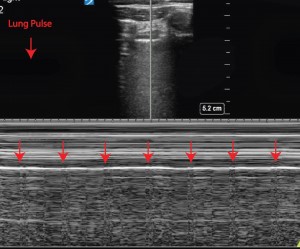

- En las atelectasias es posible encontrar el pulso pulmonar (o lung pulse) (figura 12), que consiste en la visualización de los latidos cardiacos a nivel de la línea pleural en un pulmón que no se está expandiendo.

- En una zona con atelectasias podemos encontrarnos además con ausencia de deslizamiento pulmonar.

- Si observamos una zona con un mínimo desplazamiento diafragmático debemos pensar en una atelectasia.

| Pulso pulmonar | Movimiento vertical de la línea pleural sincrónico con el latido cardiaco. Se observa en casos de apnea o ausencia de ventilación pulmonar (por ejemplo, atelectasias de todo un lóbulo). |